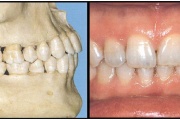

Valehambumus

Hammaste asendianomaaliad on tingitud tavaliselt arenguhäirest.